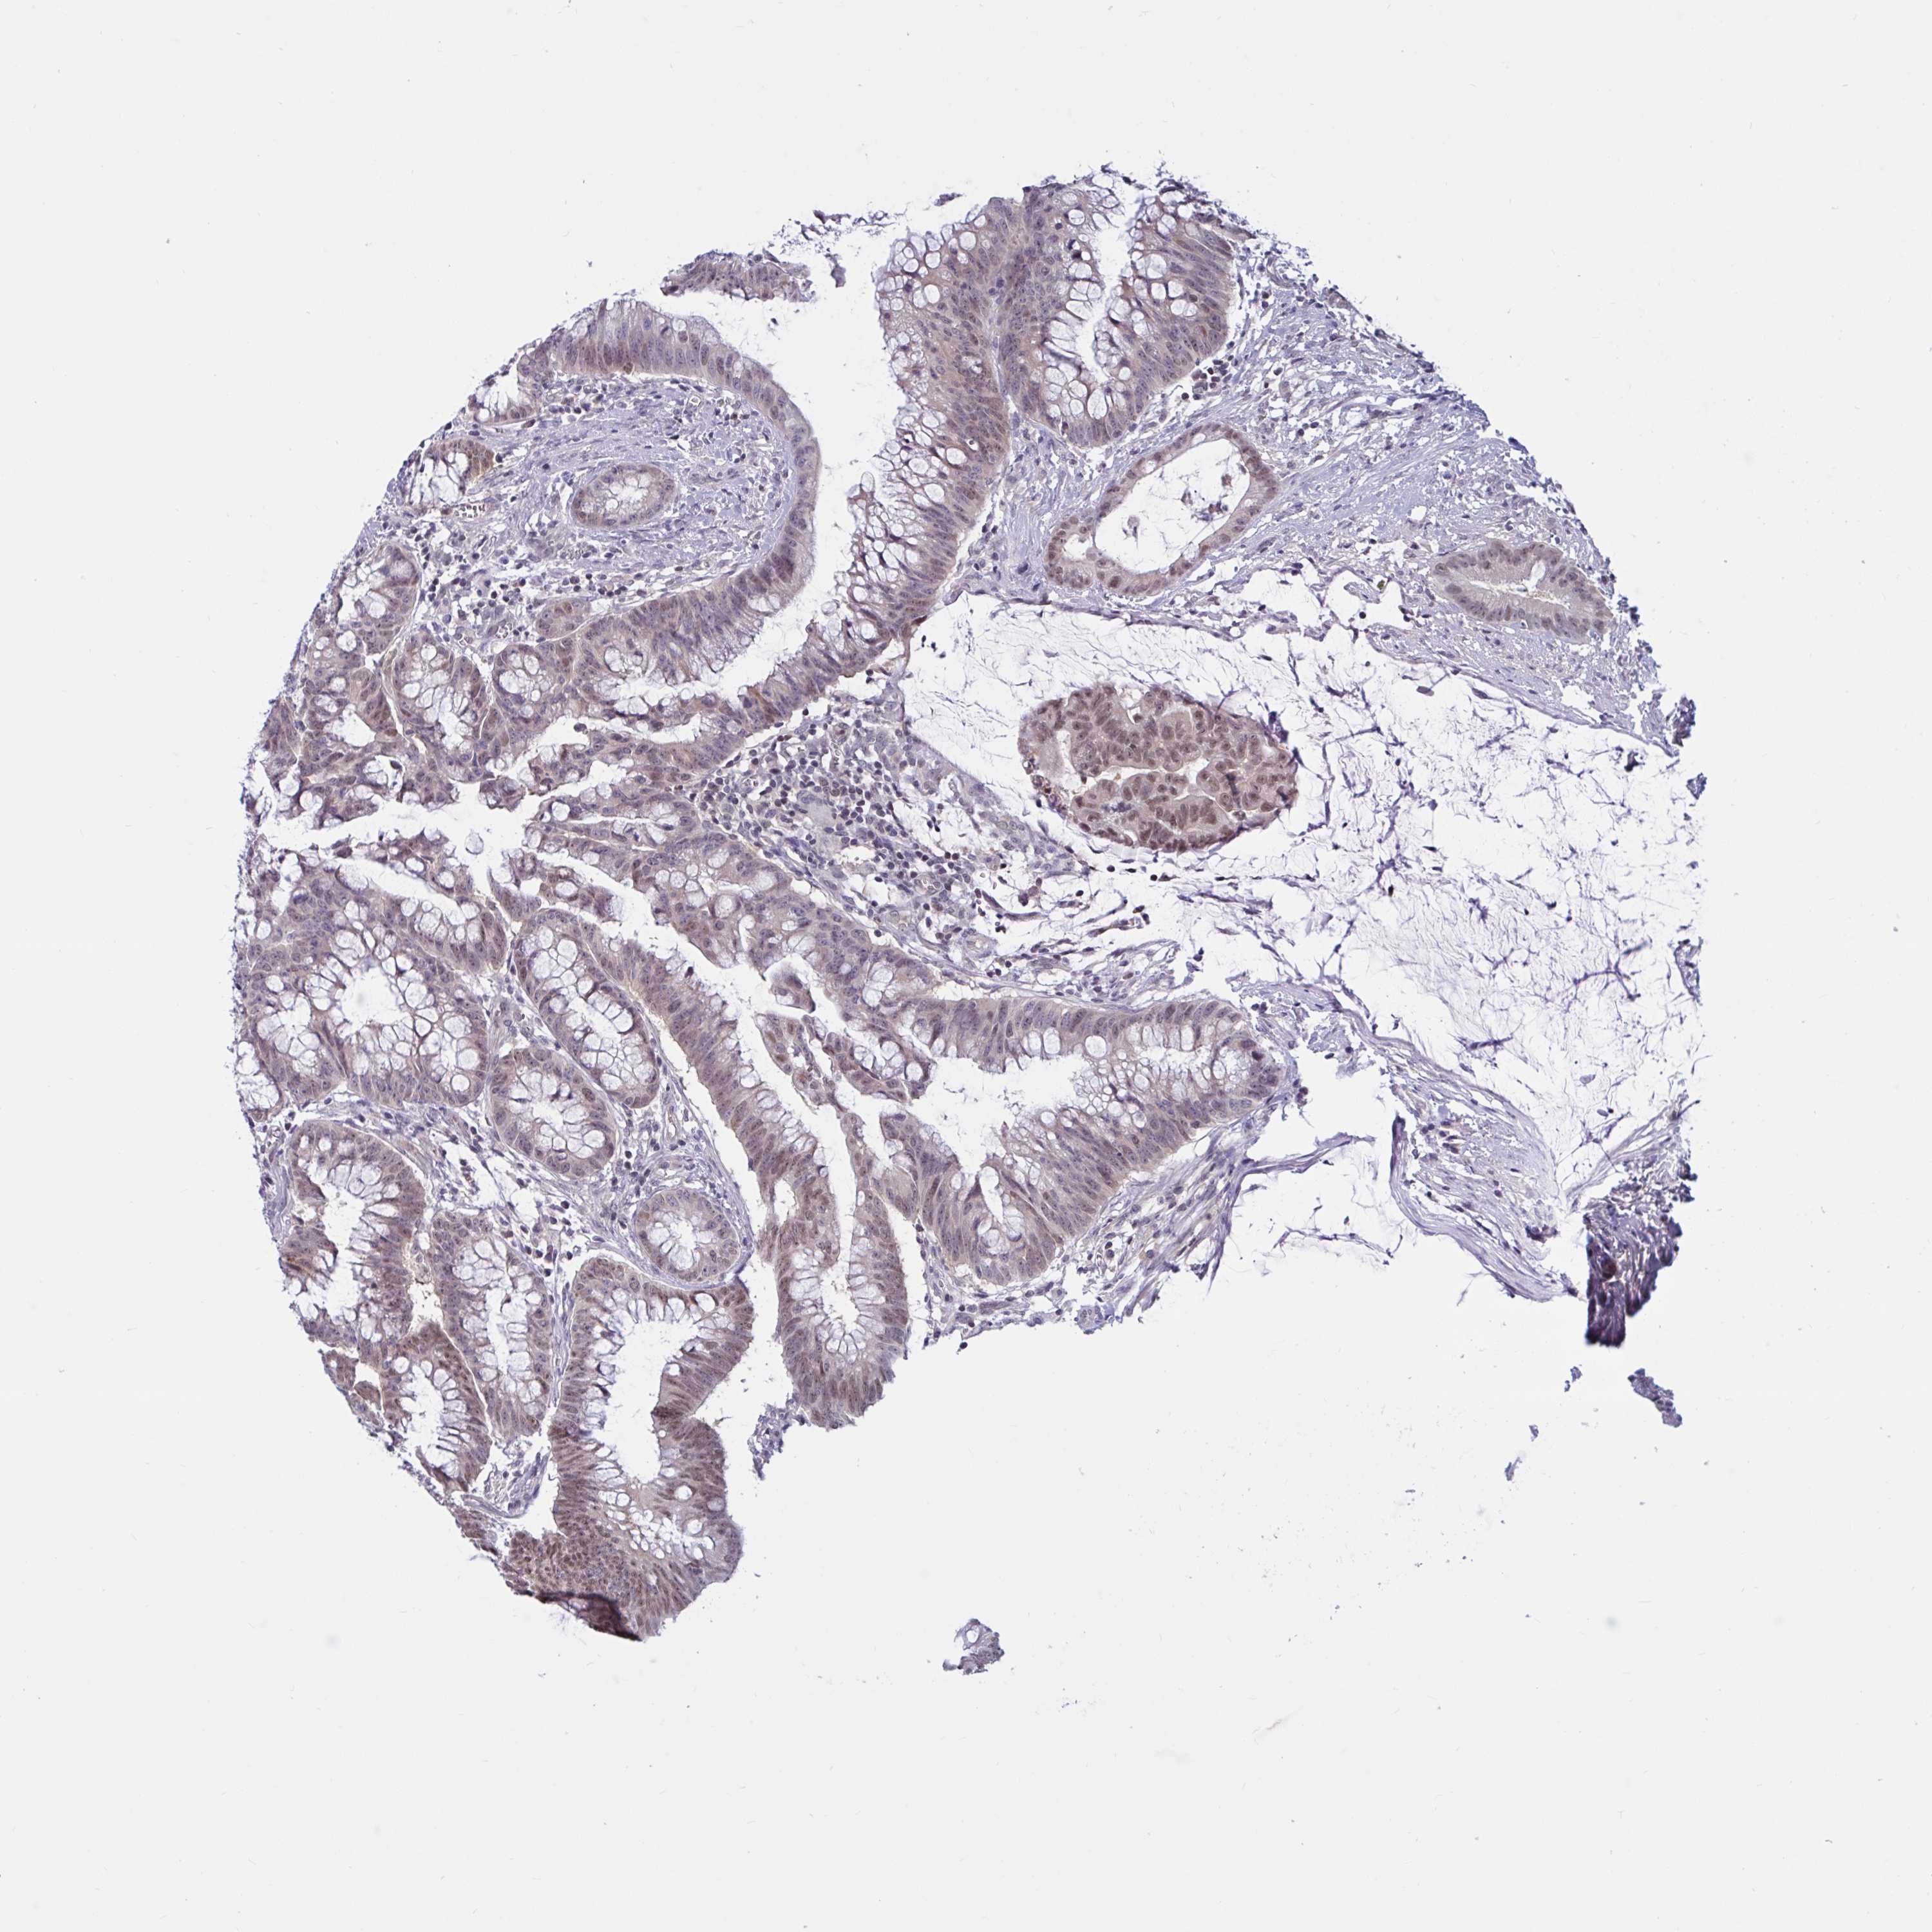

CANCER COLORECTAL CANCER Show tissue menu

Colorectal cancer

Human cancer

Colon adenocarcinoma

Rectum adenocarcinoma